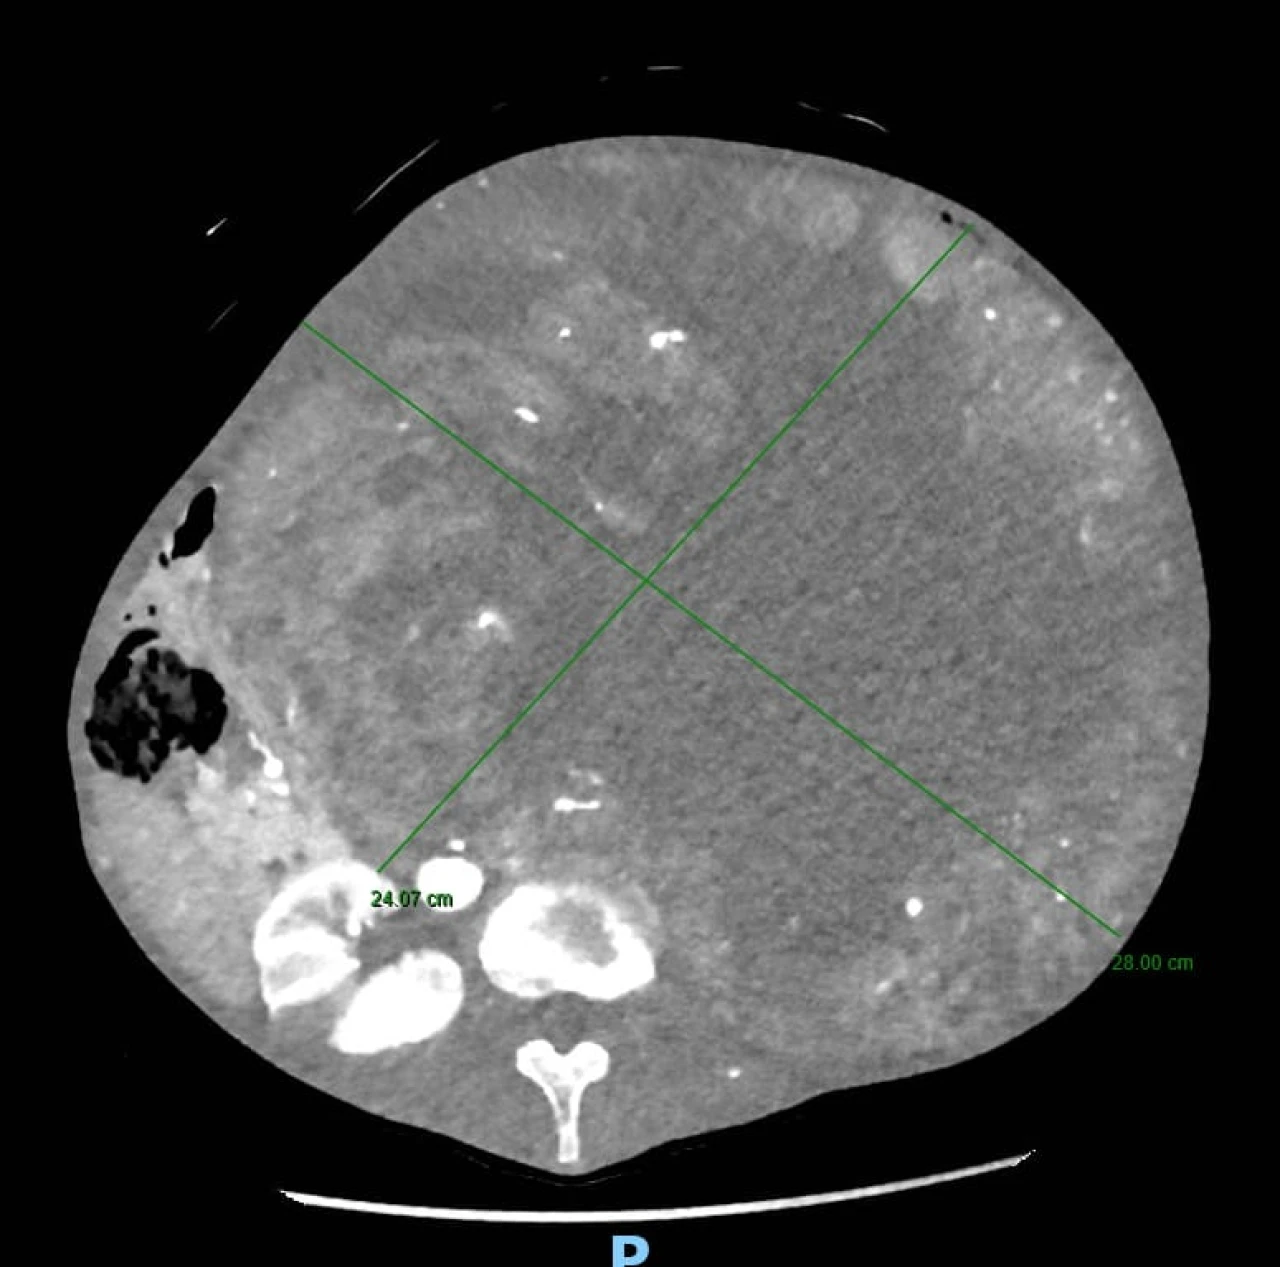

Tutto è iniziato da un disturbo apparentemente comune: la stipsi. La paziente si era infatti rivolta per la risoluzione del problema al Prof. Guido Sciaudone, Direttore della SC di Chirurgia Generale, che la aveva visitata presso l’ambulatorio di Chirurgia Colo-Rettale ed Oncologica della ASREM da lui diretto. Tuttavia, alla visita clinica era da subito apparso evidente che il sintomo stipsi era secondario alla presenza di una voluminosa massa addominale di dimensioni spropositate che i successivi accertamenti diagnostici rivelavano essere a partenza dal rene sinistro. Tale massa – paragonabile a un grosso cocomero – occupava ormai l’intera cavità addominale, comprimendo oltre all’intestino tenue ed al colon, organi importanti quali il fegato, la milza, lo stomaco, il pancreas ed il duodeno e compromettendo la circolazione sanguigna di tali strutture.

L'operazione, delicatissima, che ha richiesto estrema precisione, ha previsto diverse procedure integrate: la nefrectomia totale con l'asportazione del rene inglobato nella massa di verosimile natura eteroplastica (si è in attesa dell’esame istologico definitivo), la colectomia subtotale (cioè la rimozione di gran parte del colon in quanto ischemico in seguito all’occlusione cronica ed alla sofferenza vascolare dovuta alla compressione dei vasi da parte della massa) ed il confezionamento di una derivazione intestinale esterna per permettere la canalizzazione.